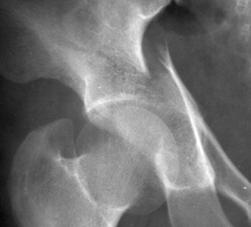

Luxatie de sold stang Luxatie de sold stang

Fractura

de cap femural Fractura de cap femural

Aspect

CT